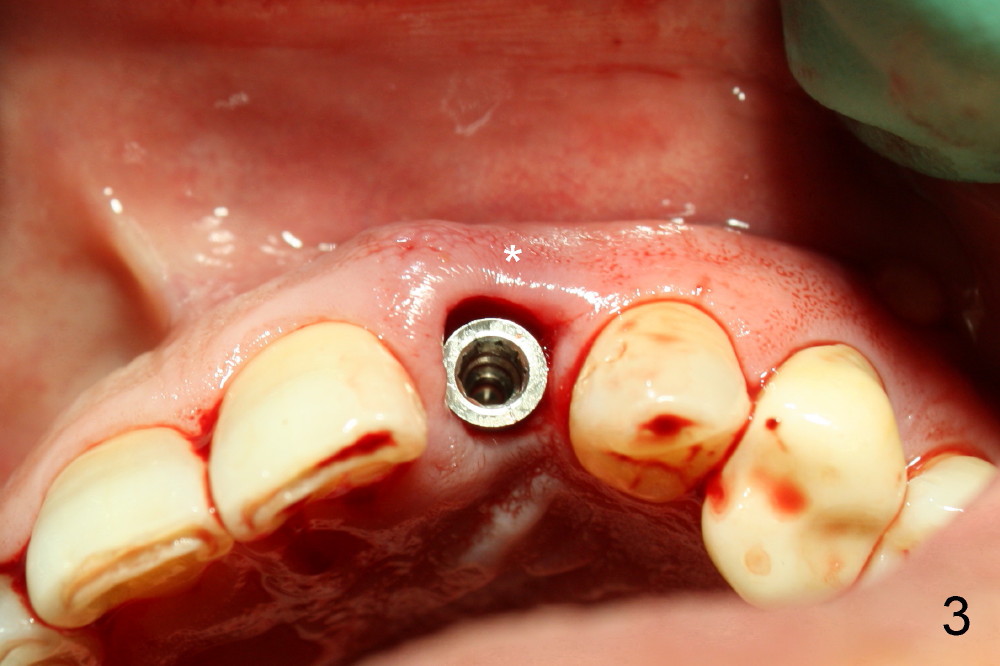

1. Place implant as lingual and apical as possible, cosmetic

3. Gingival retraction cord #2, can be overlapped, stop bleeding, push gingiva away from prep, and most important prevent Titanium shaving from being trapped in socket

4. Rinse off metal shaving with normal saline or other before cord removal, bone graft or cementation of the provisional